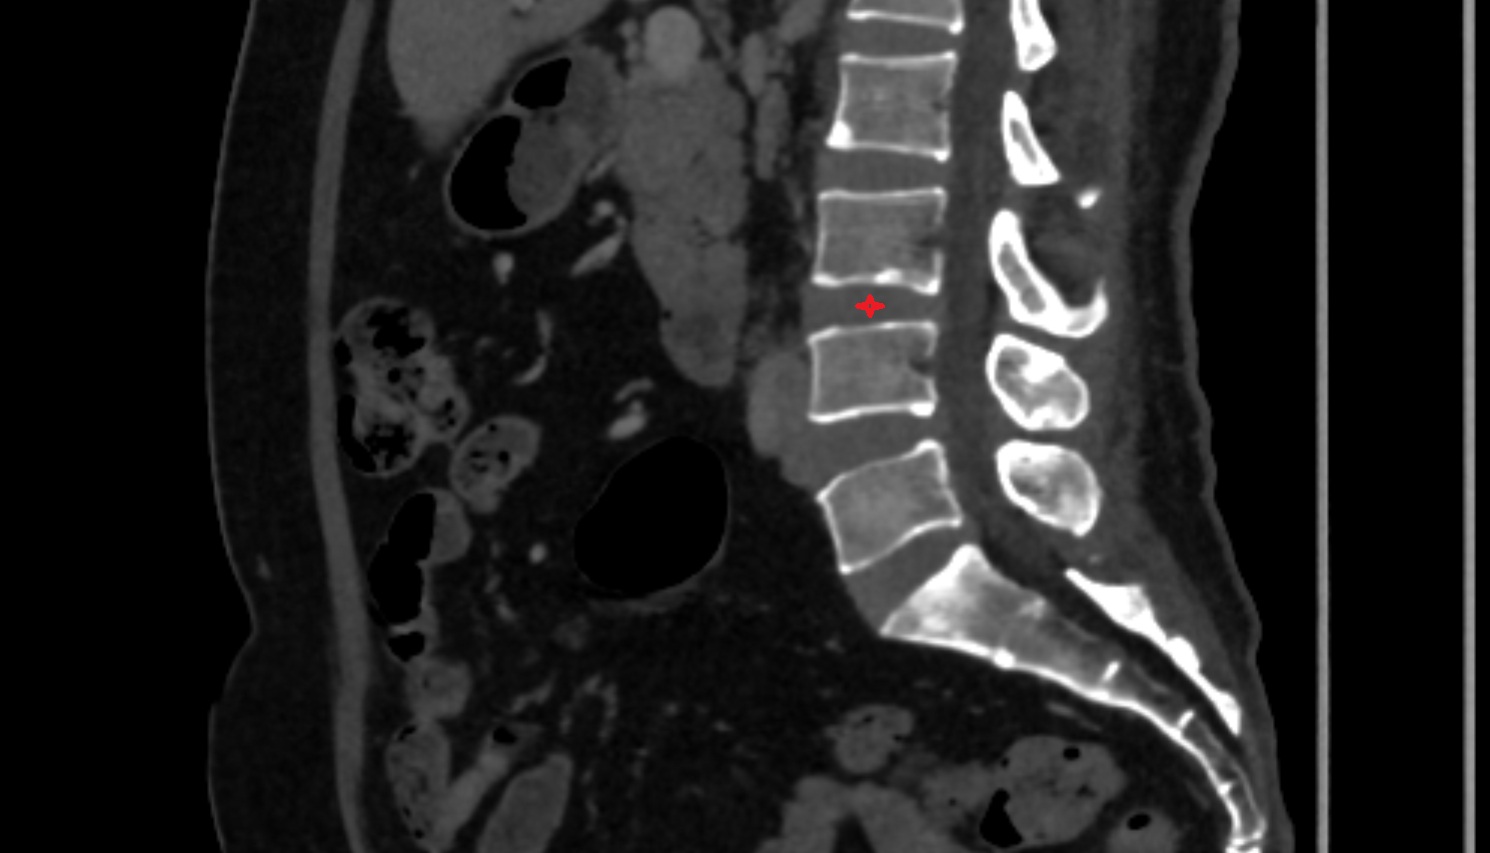

CT image

L3–L4 Intervertebral Disc  CT sagittal  anatomy  image-img-00000-00000